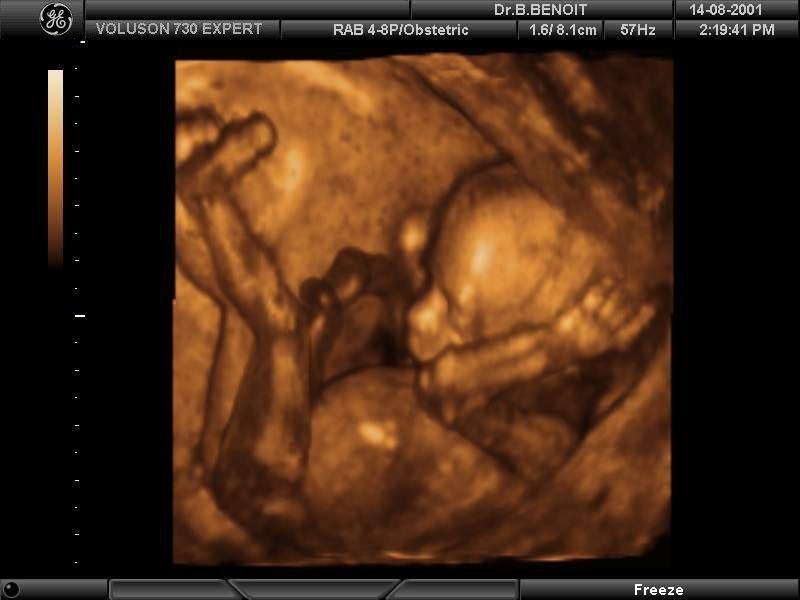

- УЗИ. Это самый популярный и достоверный способ определения пола вашего будущего крохи. Он безопасен для плода, но достоверный результат может быть получен только по истечении 23 недель беременности. На более ранних сроках существует погрешность (15-18 недель), а до этого времени способ и вовсе не информативен.

Испокон веков будущие матери задавались вопросом о том, как отличить беременность мальчиком и девочкой. Отличия искали и по форме живота, и даже исходя из стиля одежды женщины. Сегодня благодаря современному оборудованию уточнить пол ребенка не так сложно. Однако УЗИ позволяет получить эти данные не ранее 12-й недели беременности. Но что делать, если не хочется ждать так долго?